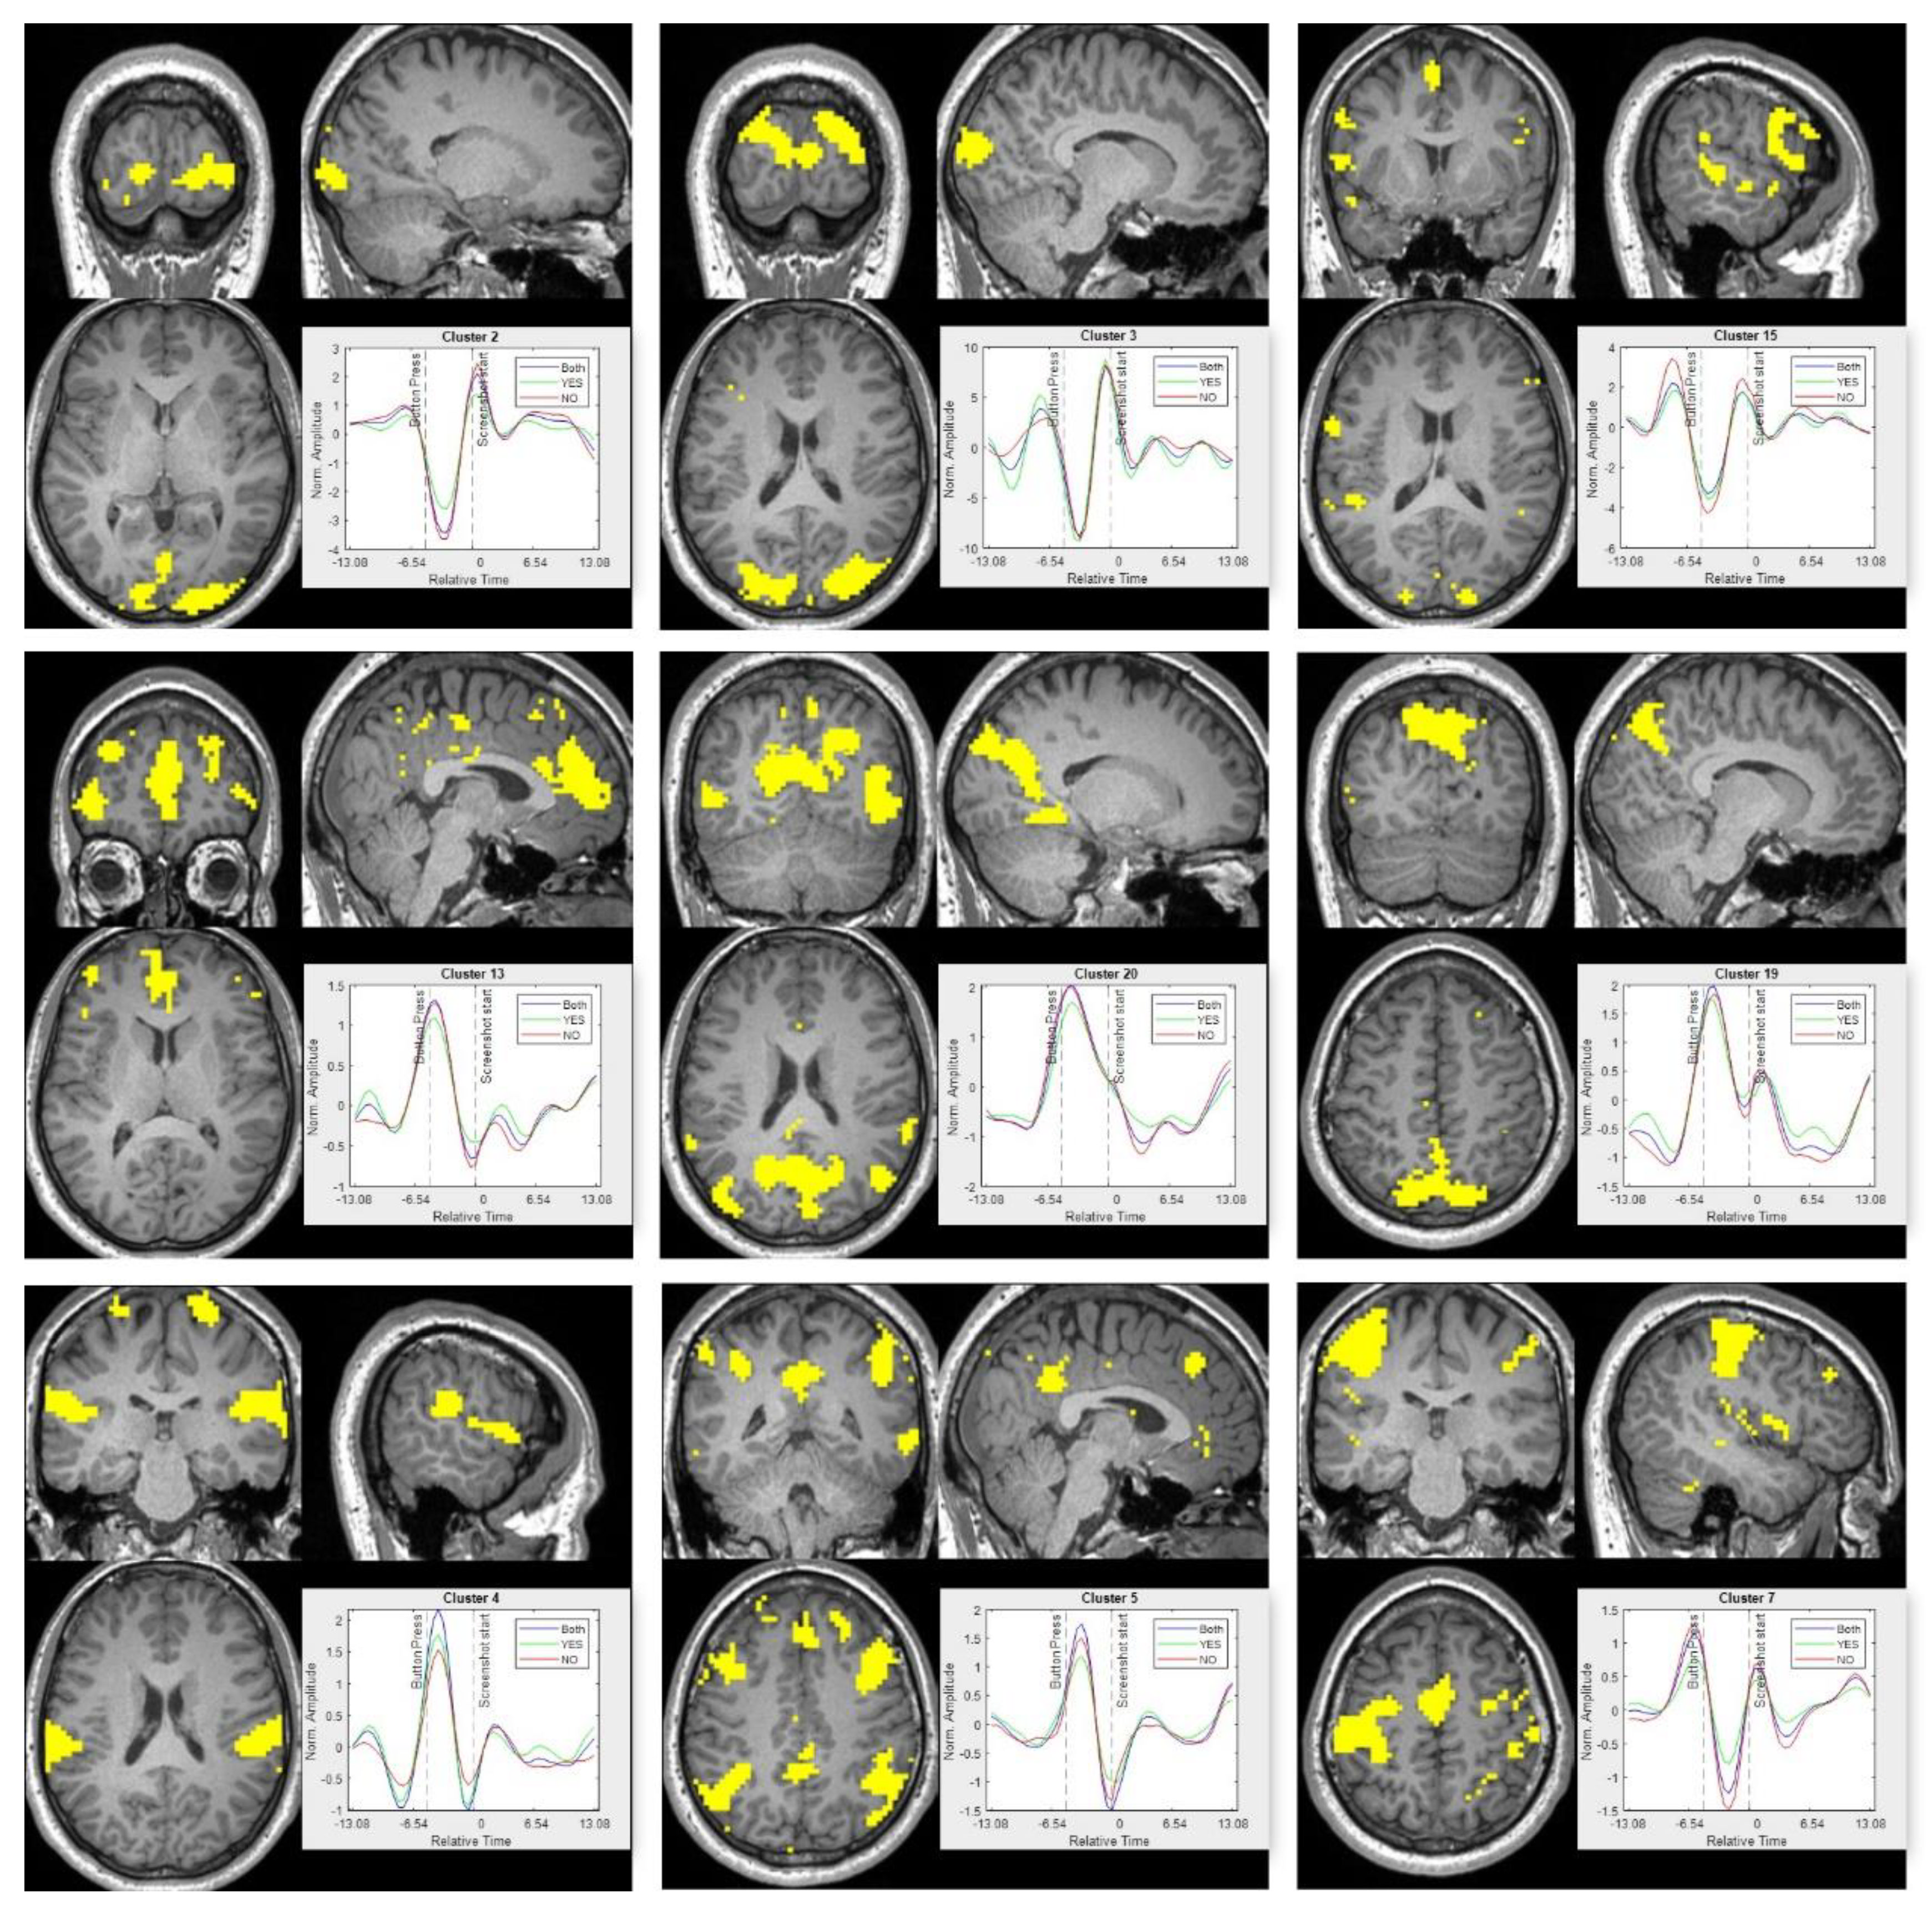

The k-means clustering results are summarized in Figure 6. The figure shows spatial clusters and the corresponding temporal response for the cluster. The cluster numbers are randomly assigned by the clustering algorithm and does not relate to the anything related to the stimulus. The cluster-level temporal response is obtained from the centroids of the k-means. Temporal response and spatial parcellation for all the 20 clusters are shown in the Appendix A section. The color scheme corresponds to the user response to the apps. The pseudo-stimulus for all the voxels were extracted for three different cases. First, for all the apps, irrespective of their download decision; second, for all the apps where the user decided to download the apps; and third, for all the apps where user decided not to download the app. The spatial cluster color and the time series color for each of the three cases are also shown in the figure. For spatial clusters, if there is an overlap in cluster for more than one cases (which was common), then the cluster color is obtained by mixing the individual colors. The k-means clustering was able to identify different brain regions based on their response to the stimuli. The activation peaks in the temporal response for different clusters corresponds to different stages in the decision-making task. The clustering approach was able to identify different brain regions in an unsupervised fashion. For example, clusters 14 and 16 correspond to the visual cortex, cluster 2 corresponds to the lingual gyrus, while cluster 18 contains the Broca and Wernicke language regions. All the above-mentioned clusters are active after the start of the stimulus during the initial phase of information gathering.

Before the decision is made (indicated by a button press), activity peaks for cluster 5. Cluster 5 consists of spatial regions belonging to the executive control network, ACC, and dorsolateral prefrontal cortex (DLPFC). DLPFC has been shown to be active towards the end of the decision-making process [5,9,17]. Because of the similar temporal response, all the different spatial regions are grouped into a single cluster. Cluster 13 consists of the left motor cortex region while cluster 8 corresponds to the DMN. Motor cortex shows activity at the end of the stimulus while the DMN shows activity during the 5 s blanking period. Finally, cluster 3 overlaps with the frontoparietal network and shows transient activity during the beginning and end of the main stimulus. The role of DMN and frontoparietal network have been discussed earlier. For clustering, it is interesting to observe that even with an unsupervised clustering approach, it is possible to extract spatial regions with meaningful interpretations.

Appendix A.4. K-Means Clusters

The spatial clusters and the corresponding time series for all 20 clusters are shown in Figure A4 and Figure A5, respectively. The spatial clusters are shown for all the apps (irrespective of the response), while the representative time series for all the clusters are shown for all three cases (irrespective of the response, only yes response and only no response to download decision).

Figure A5. Temporal for each of the 20 spatial cluster shown in Figure A4. The response for ‘yes’ apps is shown in green; ‘no’ apps is shown in red and the case for all user decision (both yes and no) is shown in blue. The x-axis represents normalized time that is centered at the beginning of new app (new stimulus), while the y-axis represents the averaged normalized amplitude.

The group-level spatial and temporal results for L1 regularization of the first difference is shown in Figure A8. The solution to the optimization using L1 regularization of the first difference was solved by an iterative process. As discussed in Appendix A.7, a modified pipeline was used to obtain group-level results. The group-level results are very similar to the results obtained using L2 regularization. The temporal smoothing of the pseudo-stimulus may be caused by the averaging of response across all the trials and participants. The positive and negative peaks time locked to the experiment design is observed. The spatial clusters 2 and 3 overlap with the visual cortex regions and the temporal response shows a positive peak at the beginning of the trial. The clusters 19 and 20 overlap with the default mode network and their temporal response peaks during the blanking period (between the button press and beginning of the new trial). As discussed earlier, the default mode network is a task-negative network, and the temporal response for clusters 19 and 20 seems to be following that trend. Spatial cluster 13 overlaps with the brain regions of DLPFC, VMPFC and ACC. The temporal response for cluster 13 peaks towards the end of the decision-making process, which is similar to results observed for L2 regularization and discussed in Section 3 above. The motor cortex overlaps with cluster 7 and the temporal response has a dominant peak towards the end of the trial as observed for results of L2 regularization.

Figure A8. Spatial and temporal results for L1 regularization of the first difference. The spatial maps correspond to k-means clusters. The cluster numbers are indicated on top of the time series subplot. The temporal plot shows the mean response of the clusters to ‘YES’ apps (green), ‘NO’ apps (red) and ‘all’ apps (blue). The temporal response is centered at the beginning of the new trial. The instance of a button press and beginning of new trial is indicated with dotted lines.